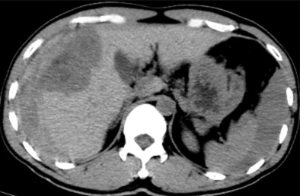

據悉,患者既往有多年乙型肝炎病史,突發右上腹劇烈疼痛入院。患者入院時血壓70/40mmHg,心率110次/分,全腹壓痛。血常規血紅蛋白87g/L,甲胎蛋白>1210 ng/ml。腹部B超檢查及CT平掃檢查示“肝腫瘤并出血,腹腔積血積液”。